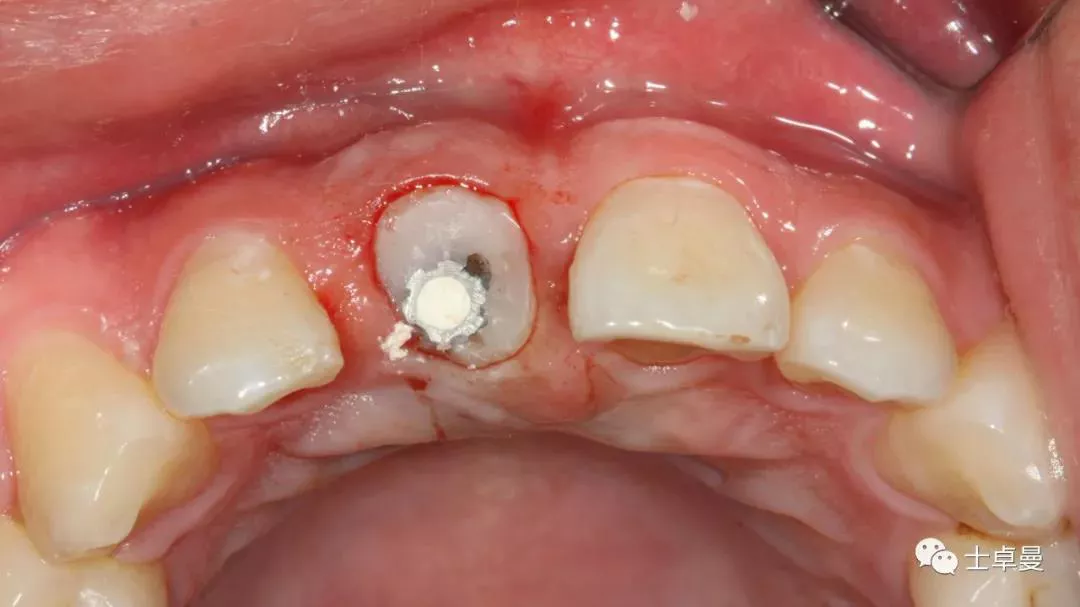

分根

拔出腭侧牙根

保留唇侧牙片

牙周探针探查牙片位置及松动度

就位种植外科导板

指示杆观察备孔三维位置

种植体植入后,植体唇侧间隙内填塞骨粉0.25g,胶原骨100mg,安放愈合帽,明胶海绵暂时封闭创面